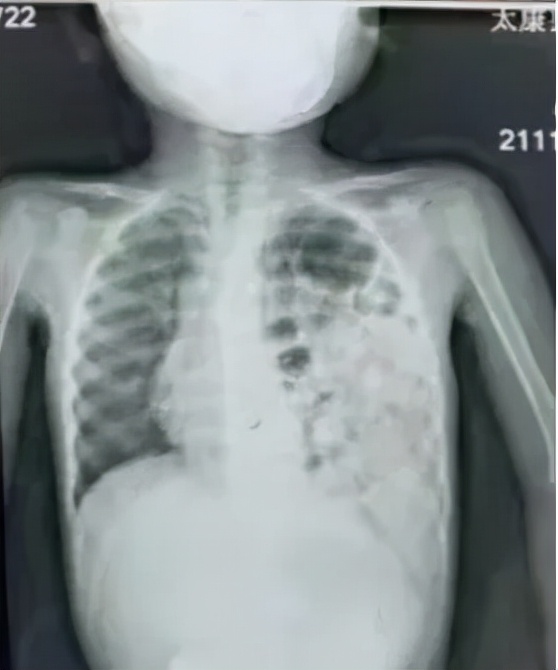

术前

在胸腔镜视野下,可看到楠楠的左侧胸腔内充满了胃和肠子,而左肺则受压变小,医生们帮助腹腔各脏器回到它们原本的位置,紧接着修补了缺损的膈肌,最后让受压的左肺重新膨开了。